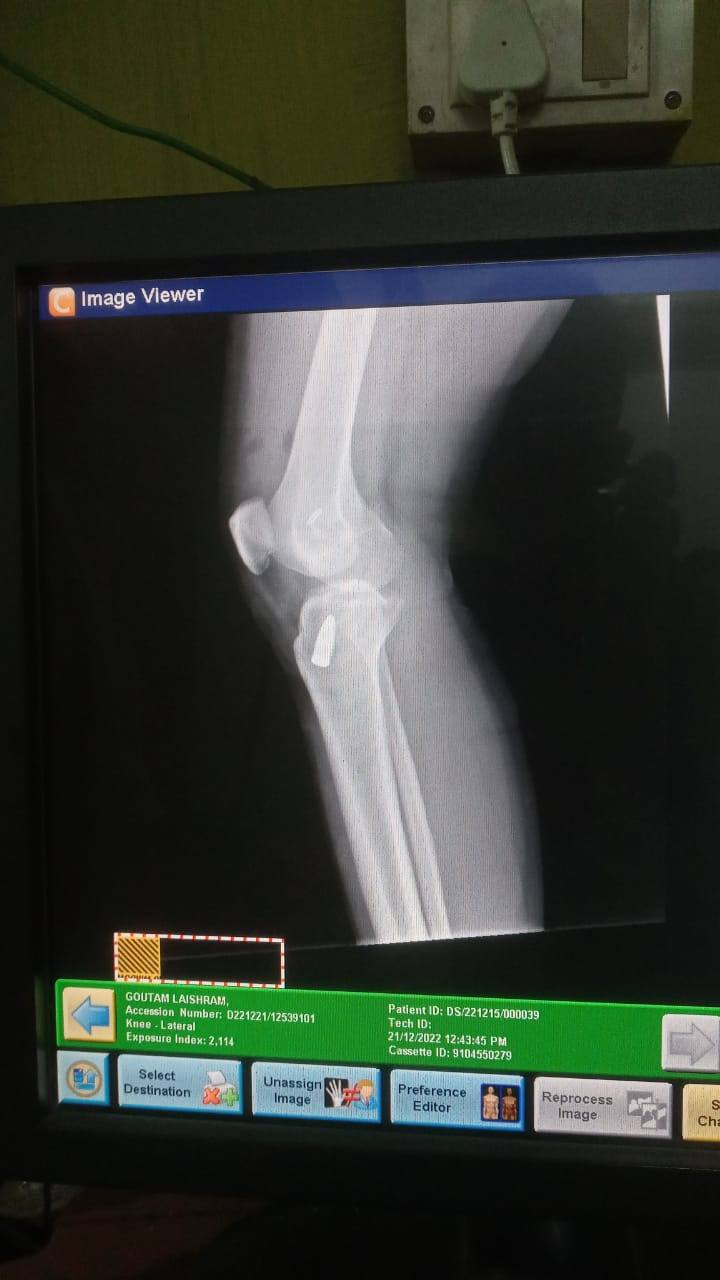

Sir, I had done my ACL surgery, with Titanium screw and titanium button ,almost 15 days ago , sir is this ok sir?